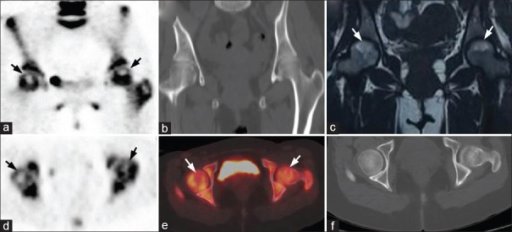

What imaging modalities are used to diagnose and stage AVN? Describe the key findings.